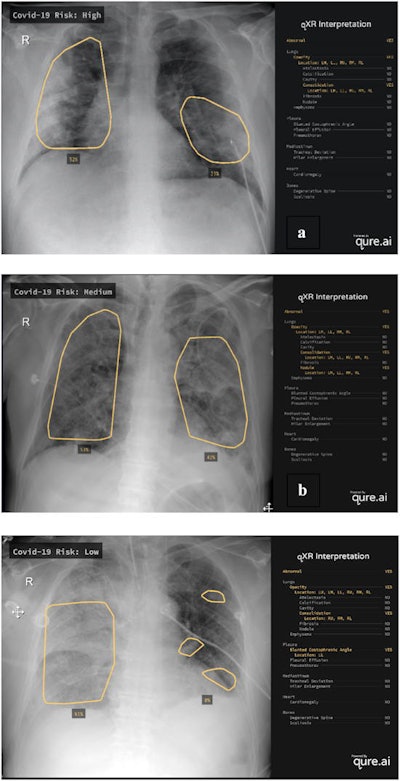

After receiving additional training on COVID-19 patients, the modified algorithm -- called M-qXR -- produces a risk score that stratifies patients into no-risk, low-risk, medium-risk, or high-risk categories for COVID-19 based on the presence of pulmonary opacities and consolidations with a bilateral and peripheral distribution, according to the researchers. The institution used the software to help stratify at-risk patients to receive further testing.

Next, the researchers compared the AI model's results with 113 patients confirmed from a PCR test to have COVID-19. After creating a co-occurrence matrix between the AI algorithm's COVID-19 risk score and COVID-19 PCR test results in 113 PCR-confirmed COVID-19 cases, the researchers also found that a medium to high-risk score yielded a positive predictive value of a positive COVID-19 PCR test result in 89.7% of cases and a negative predictive value of 80.4%.